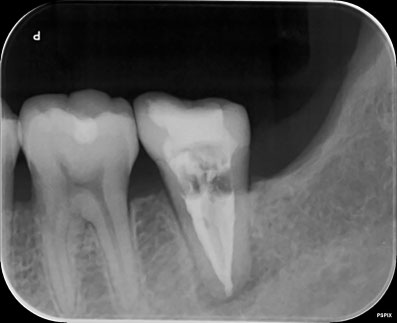

ガッタパーチャを完全に除去し、別の薬に置き換えました。別の薬が根の先まで到達しているのがわかると思います。

約1ケ月後ですが、根の先の炎症の証である透過像は、消失し、噛むと痛いなどという臨床症状も消えました。